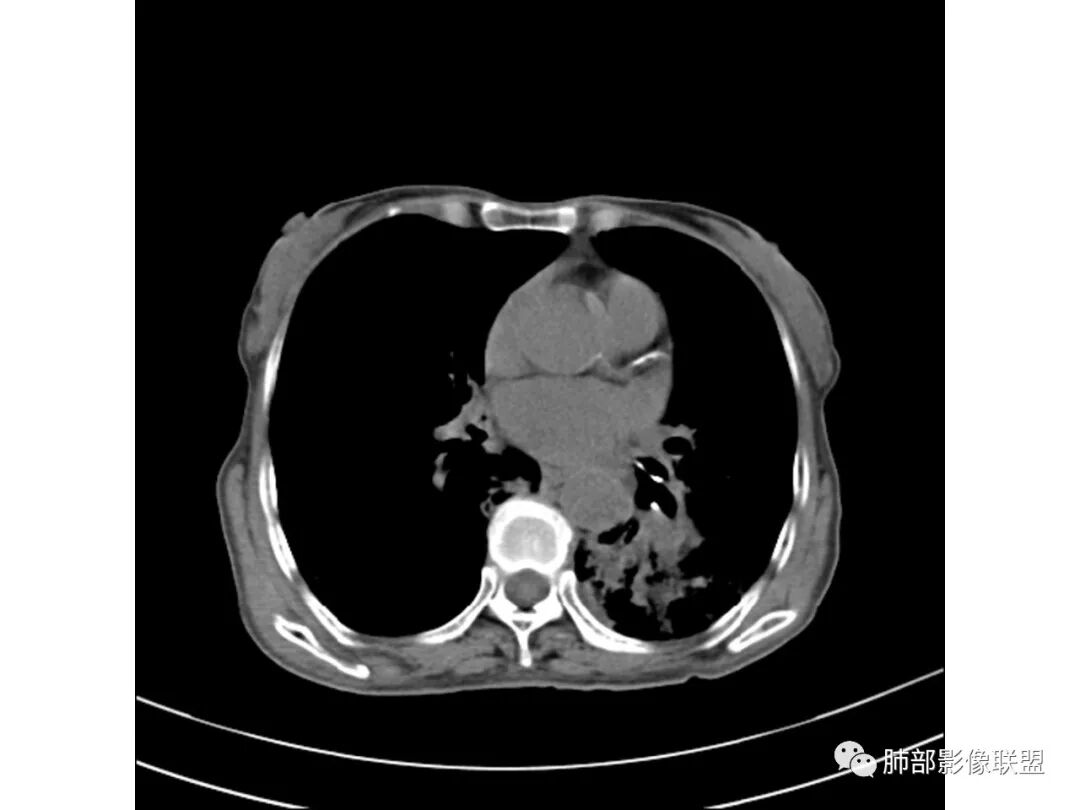

这些应该是胸水

支气管扩张、扭曲成团,附近钙化灶

肿瘤会这样吗?

宇宙星空

一般不会

纵膈也左移了

这例左下叶的体积是整体缩小的,左下叶的支气管主干稍微小一点点,然后左上叶的下舌段也有类似的病灶,然后我们看到一团乱的支气管扩张,但它有特点,边缘凹凸不平。那什么样的支气管扩张边缘会如此凹凸不平呢,等我截个图:

看最后一幅图,上面这个支气管,有可能是淋巴瘤,为什么?他的支气管稍扩张,直达远端、实变。

首先这幅图支气管很多地方是扭曲的,远端扩张的特别厉害。如果是肿瘤,首先考虑淋巴瘤,因为支气管可直达远端,稍扩张,但是它的前提是周围要实性占位的,而且它不会这样扭曲变形。我们看这个病例的支气管扩张,它支气管扩张占大部分区域,中间稍有些实性的结构,这就不符合了。这幅图你会发现所有支气管都是扩张的,实性部分偏少,外围胸水。所以我更倾向慢性炎性病变,能够引起支气管扩张的炎性病变有哪些?结核?NTM?支扩伴感染?大方向是慢性炎性病变。这些左下肺播散出来的病灶,咳中等量黄浓痰,我考虑还可能合并细菌感染。